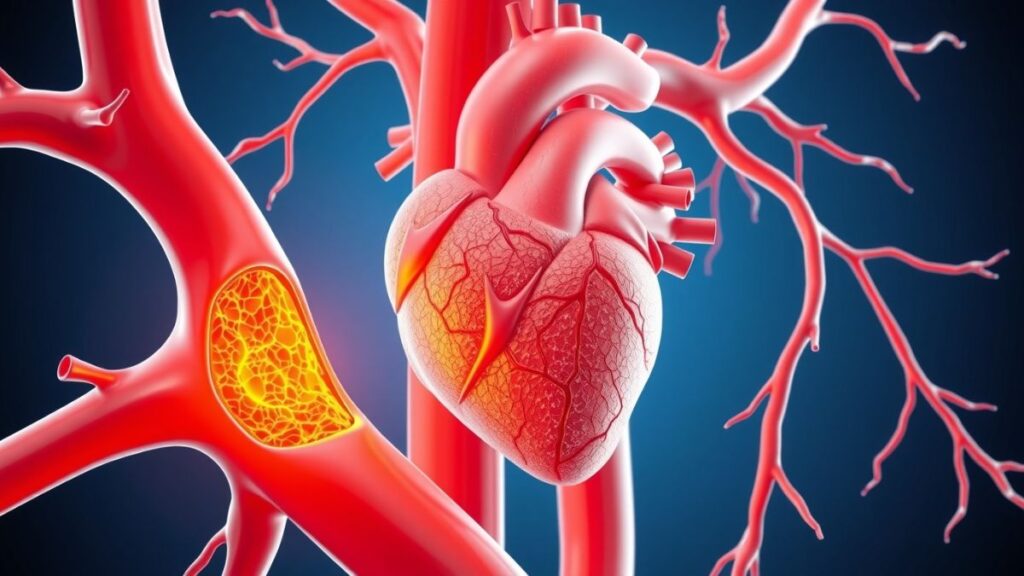

कोलेस्ट्रॉल हमारे हृदय को कैसे प्रभावित करता है?

जब शरीर में खराब कोलेस्ट्रॉल (LDL) बढ़ता है, तो यह धीरे-धीरे हमारी धमनियों की दीवारों पर जमने लगता है। इससे नसें सिकुड़ जाती हैं और खून का बहाव कम हो जाता है। यही कारण है कि कोलेस्ट्रॉल का हार्ट पर प्रभाव इतना खतरनाक माना जाता है। जब हृदय तक पर्याप्त ऑक्सीजन वाला रक्त नहीं पहुंचता, तो सीने में दर्द, घबराहट और हार्ट अटैक का खतरा बढ़ जाता है।

समय रहते ध्यान न दिया जाए, तो यही स्थिति हार्ट ब्लॉकेज और स्ट्रोक तक का कारण बन सकती है।